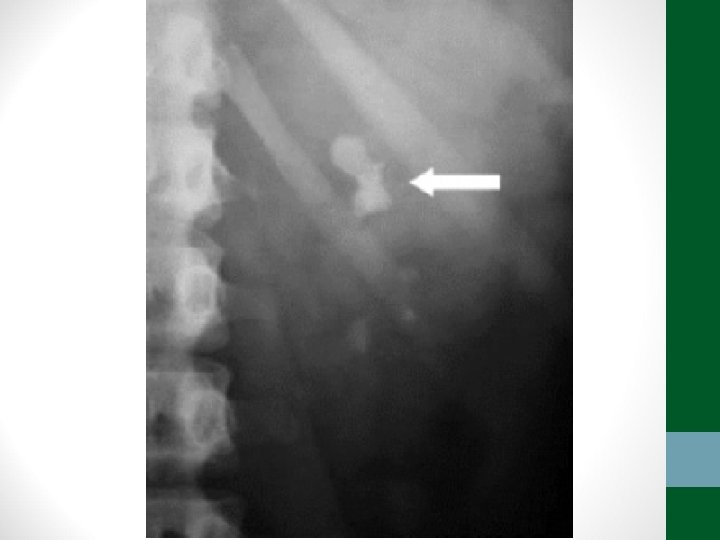

Exames de Imagem • Abdome Agudo Inflamatório: • Radiografia simples de abdome: decúbito, ortostase e cúpulas diafragmáticas • USG Abdome total é diagnóstico na maioria dos casos • TC de abdome com contraste VO e EV se USG não esclarecer ou em forte suspeita de diverticulite aguda ou pancreatite aguda grave

Exames de Imagem • Abdome Agudo Perfurativo: • Radiografia simples de abdome: decúbito, ortostase e cúpulas diafragmáticas • USG Abdome não ajuda! • TC de abdome com contraste VO e EV se Raio-X não esclarecer

Exames de Imagem • Abdome Agudo Obstrutivo: • Radiografia simples de abdome: decúbito, ortostase e cúpulas diafragmáticas • USG abdome não ajuda! • TC Abdome com contraste VO e EV se não houver resolução em 48 h de tratamento clínico ou de acordo com suspeita clínica

Exames de Imagem • Abdome Agudo Vascular: • Radiografia simples de abdome: decúbito, ortostase e cúpulas diafragmáticas • USG abdome não ajuda! • TC Abdome com contraste EV e VO – angio. TC (fase arterial e portal) é o melhor exame

Exames de Imagem • Abdome Agudo Hemorrágico: • Radiografia simples de abdome: decúbito, ortostase e cúpulas diafragmáticas (apenas para descartar outras causas) • USG Abdome é o exame mais importante, pode ser necessária USG transvaginal • TC de Abdome em casos selecionados